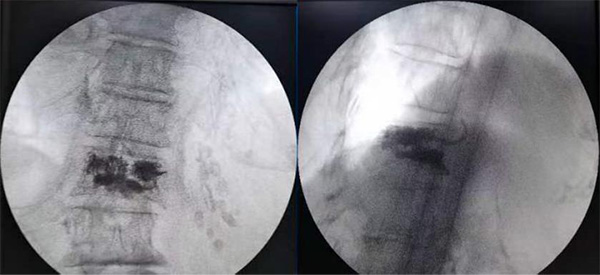

图为手术结束,骨水泥均匀分布

患者手术结束后即感疼痛明显缓解,可自主活动,手术当日顺利出院。次日电话随访,患者已在保护下离床站立和行走。